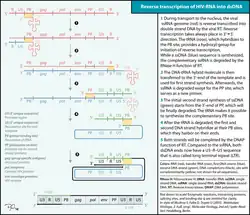

Replicação e transcrição

Pouco depois do capsídeo viral penetrar na célula, uma enzima denominada transcriptase reversa liberta o genoma ARN de cadeia única das proteínas virais, e copia-o para uma molécula complementar de ADN.[52] O processo de transcrição reversa é extremamente predisposto a erros e as mutações daí resultantes podem provocar resistência aos anti-virais ou permitir ao vírus evadir o sistema imunitário. A transcriptase reversa tem também atividade de ribonuclease, que degrada o ARN viral durante a síntese de ADN complementar, assim como atividade de ADN polimerase ADN-dependente, capaz de criar ADN de sentido positivo a partir do ADN complementar de sentido negativo.[53] Juntos, o ADN complementar e o seu complemento forma um ADN viral de cadeia dupla que é assim transportado para o núcleo celular. A integração do ADN viral com o genoma das células anfitriãs é realizada por outra enzima viral, denominada integrase.[52]

O ADN viral, agora integrado na célula, pode permanecer dormente durante a fase latente da infeção.[52] De forma ao vírus poder ser produzido de forma ativa, têm que estar presentes determinados fatores de transcrição, o mais importante dos quais o NF-κB (factor nuclear kappa B), que é depois supra-regulado quando os linfócitos T são ativados.[54]

Durante a replicação viral, o AND proviral integrado é transcrito para ARNm, que é depois reorganizado através de splicing em partes mais pequenas. Estas partes são exportadas do núcleo para o citoplasma, onde são transcritas para as proteínas reguladoras Tat (que incentiva a produção de novos vírus) e Rev. À medida que as proteínas Rev recém-formadas se acumulam no núcleo, vão-se ligando ao ARNm viral e permitem ao ARN que ainda não sofreu splicing abandonar o núcleo, onde de outra forma são retidos até sofrerem splicing.[55]